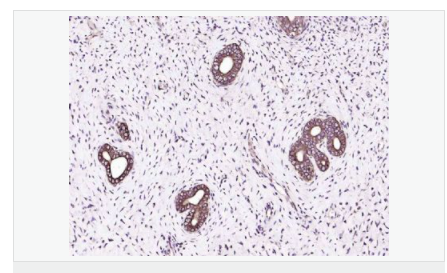

| 產品應用 | WB=1:500-2000 ELISA=1:5000-10000 IP=1:20-100 IHC-P=1:100-500 IHC-F=1:100-500 IF=1:100-500 (石蠟切片需做抗原修復) not yet tested in other applications. optimal dilutions/concentrations should be determined by the end user. |

| 英文名稱 | IGF 1 |

| 中文名稱 | 胰島素樣生長因子1抗體 |

| 別 名 | IBP1; IGF 1; IGF I; IGF-1;IGF IA; IGF IB; IGF1; IGFI; IGFIA; Insulin like growth factor 1 (somatomedin C); Full=Insulin-like growth factor I; Insulin Like Growth Factor 1; Insulin like growth factor IA; Insulin like growth factor IB; Mechano growth factor; MGF; Mechano growth factor; MGF; Somatomedia C; Somatomedin C; IGF1_HUMAN. |